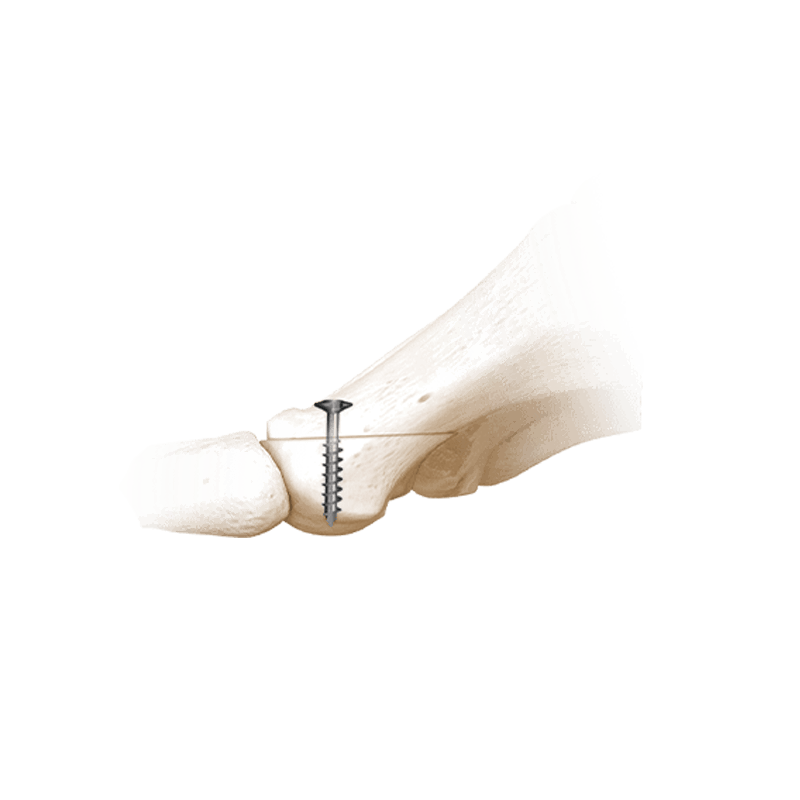

Fixation Devices - Compression Hardware

IBS™-B Beveled Screw System

IBS™-B Beveled Screw System delivers the strength, control, and versatility your MIS workflow demands.